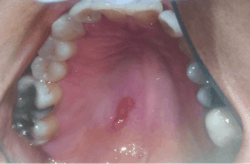

Clinical examination of her oral cavity revealed multiple missing teeth in all four quadrants, and a 3.5 cm erythematic lesion extending from the posterior hard palate to 1 cm onto the soft palate (figures 7,8).

The patient self-reported a height of 5’5” and weight of 125 pounds, BMI 20.8. Oral examination showed a fully dentate individual. Mandibular third molars Nos. 17 and 32 were partially erupted, and both exhibited signs of pericoronitis with negative lymphadenopathy. Her dental history included several amalgam restorations on her posterior teeth. A 4 mm in diameter, erythematous, nonulcerated lesion was noted on the palate (figure 9).